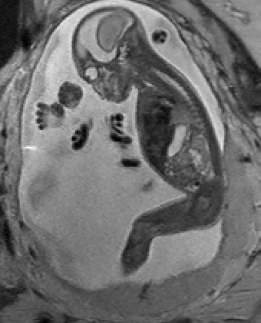

Reconstruction of Fetal Organs: Exemplary PVR and SVR reconstructions under motion introduced by kicking of the fetus are shown in Fig. 11. PVR reconstruction results show an improved visual appearance and less blurring in the region with severe motion artifacts (arrow). An example of a challenging clinical case with a kidney malformation in one of twin fetuses, is shown in Fig. 8. Our clinical partners confirmed that such complications are easier to examine and to quantify after PVR-based reconstruction.